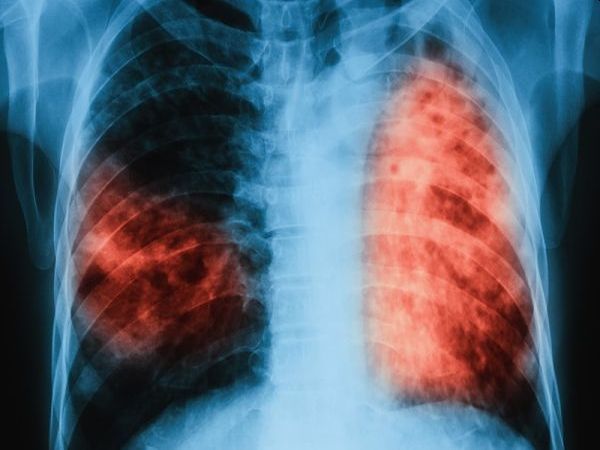

...... лекарствената резистентност. Туберкулозата се разпространява чрез продължителен близък контакт със заразен човек, когато той кашля, киха или говори, но не се заразява лесно чрез случаен контакт.

Туберкулозата най смъртоносната инфекциозна болест в света се разпространява във Великобритания Случаите

...... от всички смъртни случаи в Обединеното кралство.Но тя продължава да бъде най-смъртоносната инфекциозна болест в света, която през 2023 г. уби около 1,25 млн. души.